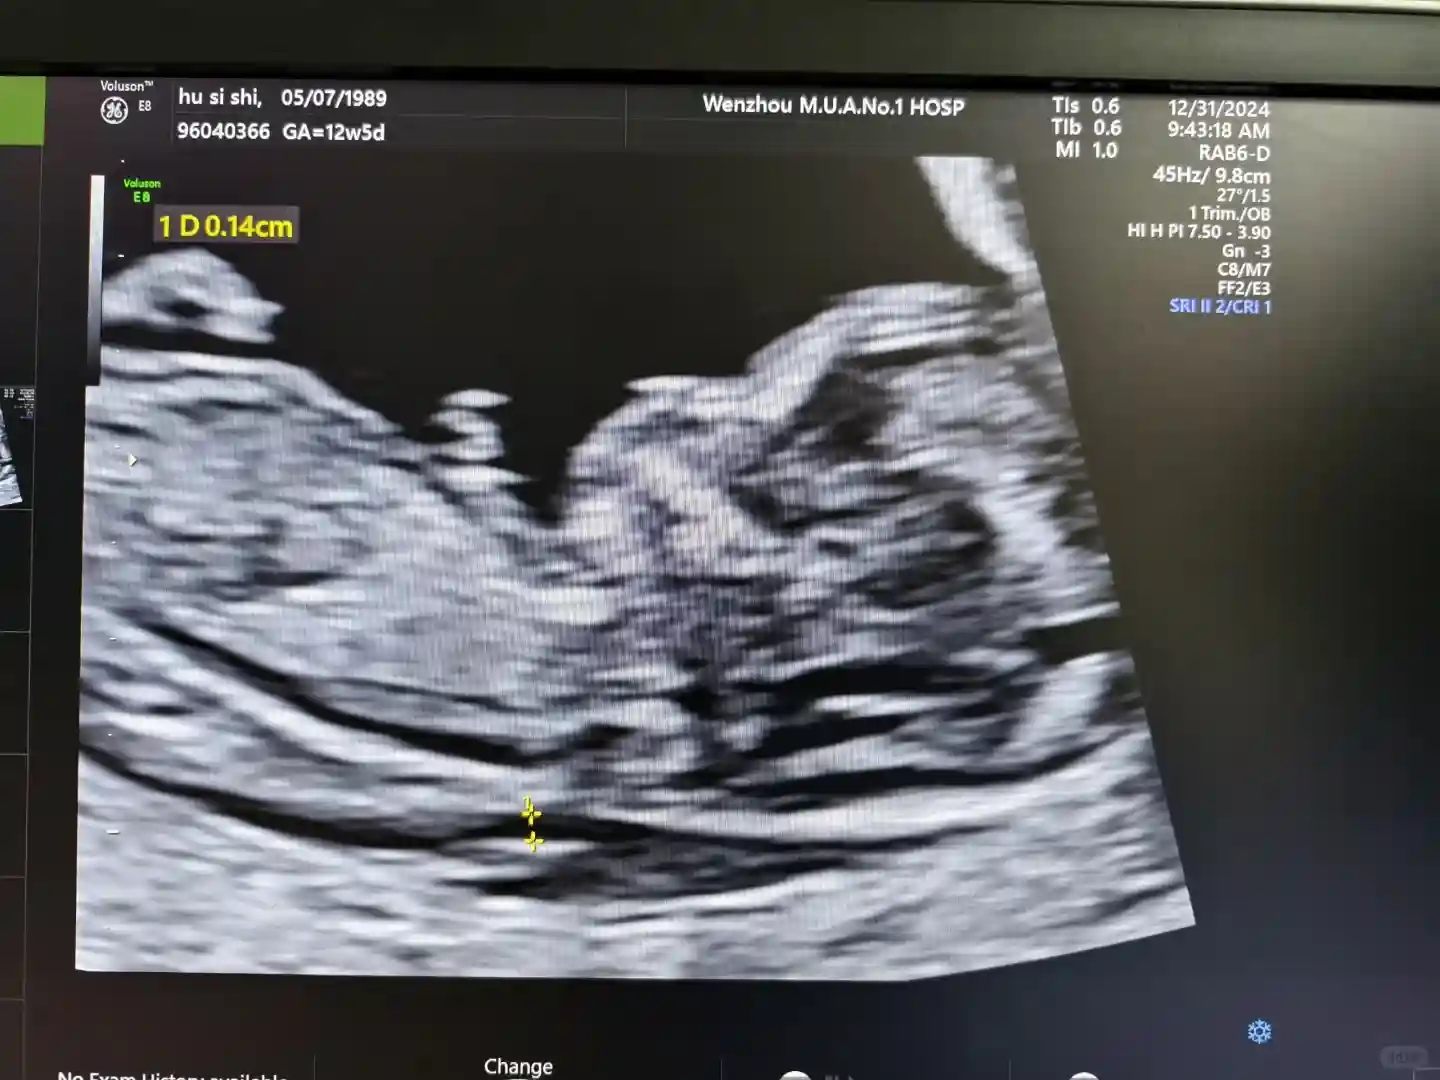

上午做NT的是个50多岁的男医生,本来还感觉怪怪的,但是医生很健谈,给人感觉是个快乐的小老头,能感受到他在让我放松,超声过程一直找话跟我聊,也特别细心,超声做完之后还主动给我拍宝宝照,感动。

NT的结果先给新院生殖中心的杨主任看过,给我发了生殖中心毕业证书,以后就按计划进行产检就好了。下午再回瑞安给人民医院的蔡丽梅医生诊断,总的来说宝宝发育很快,超声孕龄都13w+2了。。本来担心宝宝会不会头围太大了(80mm),但是医生们都说长得快是好事,要高兴。

NT检查到肌瘤最大只有4公分多,相比前两次小了3公分,虽然很奇怪,不大反小,但是医生说就当是变小了,都是好事,那就听医生的。再是因为高龄的关系,需要无创穿刺二选一,考虑到我的这批试管胚胎数量与质量过优,卵子质量理应不会差于年轻人,就决定先做无创,若没有高风险就不做穿刺。